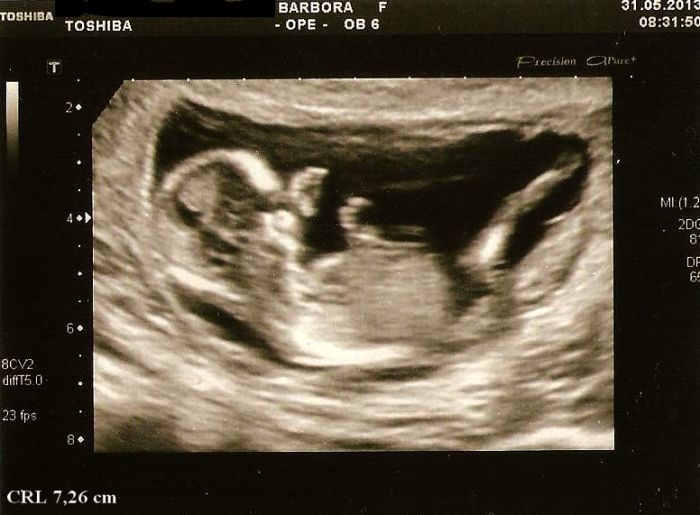

Hned jak zapnula utz začala se smát, protože mimčo stálo na hlavě(bože co z něj vyroste)

Pak ho trošku poškádlila, tak zaujal normální polohu a mohli jsme měřit. CRL máme 7,26cm a odpovídáme 13+3tt, projasnění bylo 1,3, takže prý v pořádku a stehenní kostička meřila 1 cm..Dr.mi všechno krásně popisovala a přibližovala, hlavně na obličejíčku a mrňous u toho sebou aktivně mrskal a ukazoval nám jak má dlouhý nožičky a pak se dr. smála a říká,,a teď si cpe ručičky do pusinky''..

Nakonec k mému překvapení přepla na 3D(4D) a mrňous se chvilku schovával za ručičky a pak zase mával, překvapilo mě, že to už takhle brzo bylo poměrně hezky vidět a nakonec jsme dostali 4 fotečky úplně zadarmo k ceně screeningu a z toho tři 3D..Byl to vážně úžasný zážitek a za ty peníze to určitě stálo

Přikládám 3 otečky mrňouska,první je z kontroly u mého dr.jak tam hačá,na té další se musím smát jak ukazuje chodidlo a druhou nohou se snaží prokopnout ven z bříška